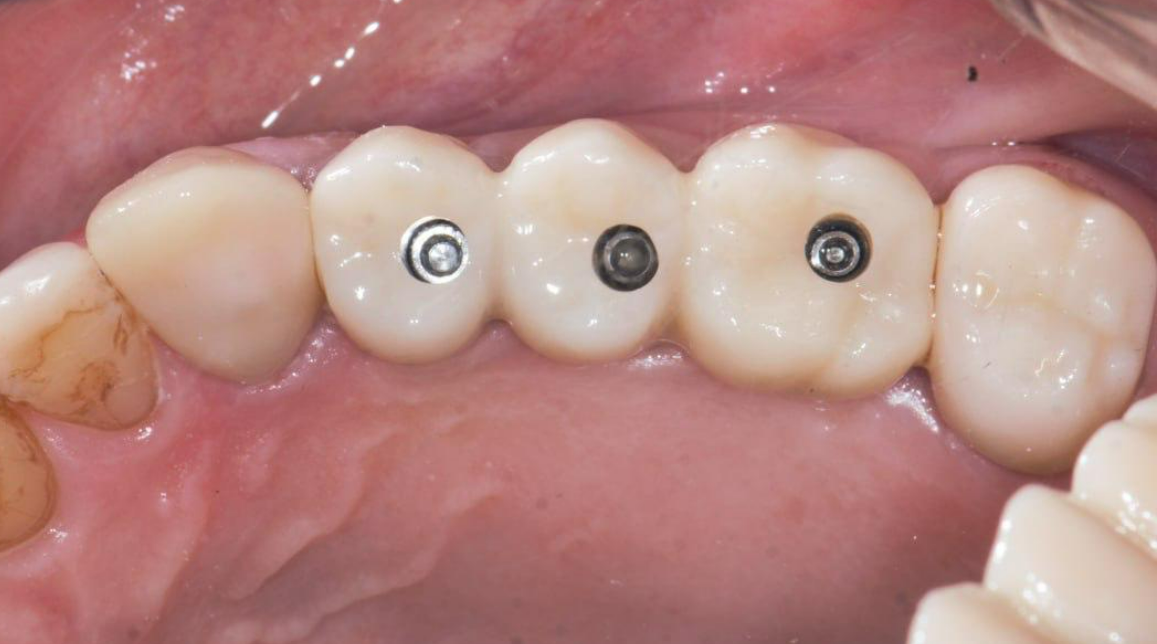

The screw-retained zirconia bridge and the crowns on teeth 13 and 17 show a precise fit, as seen in the photo below.

The completed restoration, with sealed screw access holes, is aesthetically pleasing and anatomically correct. Masticatory function is fully restored, and the patient is completely satisfied with the result.

The gingival contour around the prosthesis is well-defined; the papillae completely fill the embrasures, and a band of attached keratinized gingiva is clearly visualized and anatomically correct.